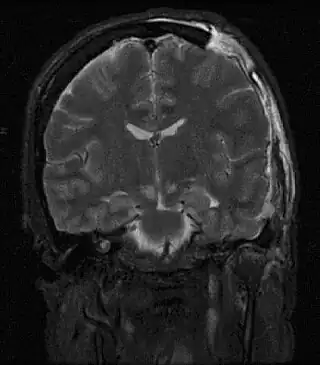

![]() Resonancia magnética mostrando lesión causada por hernia cerebral. | ||

Una hernia cerebral es una protrusión de un compartimiento craneal a otro a consecuencia de una expansión rápida de la presión intracraneal.

En una hernia cerebral (en castellano, la palabra correcta es «hernia», ya que la palabra herniación es un anglicismo que tendría el mismo significado y no es aceptada por la RAE) el cerebro puede así "herniarse" por debajo de la hoz del cerebro, en la cisura interhemisférica, a través del agujero del "tentorium cerebelli" o tienda del cerebelo o también a través del foramen magnum del hueso occipital en la base del cráneo por donde penetra la médula espinal.[1] Una hernia cerebral puede ser causada por varios factores que aumentan la presión intracraneal, como en el caso de edema o una lesión traumática del cerebro. Debido a que una hernia del cerebro produce tan elevada presión sobre porciones del cerebro, este es un trastorno a menudo fatal y una emergencia médica.[1]